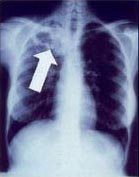

Tuberculosis creates cavities visible in x-rays like this one in the patient's right upper lobe.

In active pulmonary TB, infiltrates or consolidations and/or cavities are often seen in the upper lungs with or without mediastinal or hilar lymphadenopathy or pleural effusions ( tuberculous pleurisy). However, lesions may appear anywhere in the lungs. In disseminated TB a pattern of many tiny nodules throughout the lung fields is common - the so-called miliary TB. In HIV and other immunosuppressed persons, any abnormality may indicate TB or the chest X-ray may even appear entirely normal.[citation needed]

Abnormalities on chest radiographs may be suggestive of, but are not necessarily diagnostic of, TB. However, chest radiographs may be used to rule out the possibility of pulmonary TB in a person who has a positive reaction to the tuberculin skin test and no symptoms of the disease.[citation needed]

Cavitation or consolidation of the apexes of the upper lobes of the lung or the tree-in-bud sign[7] may be visible on an affected patient's chest X-ray.[1] The tree-in-bud sign may appear on the chest CTs of some patients affected by tuberculosis, but it is not specific to tuberculosis.[7]